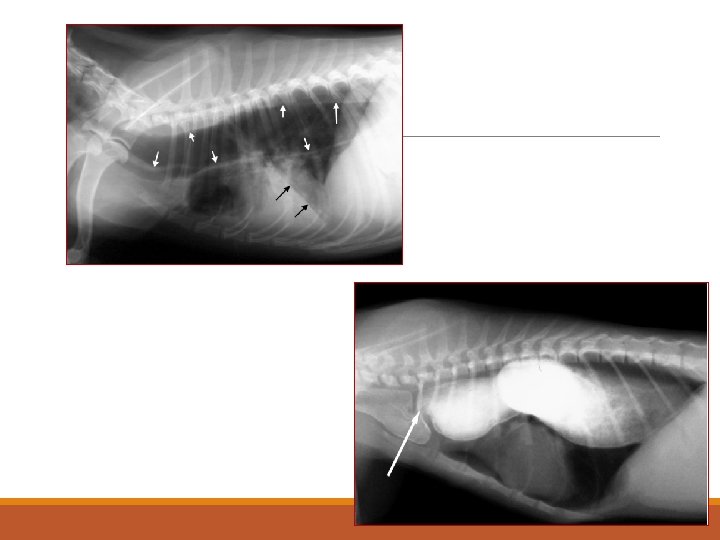

Intussuception

Bladder images demonstrating a mass infiltrating the ventral bladder wall. Negative Double contrast